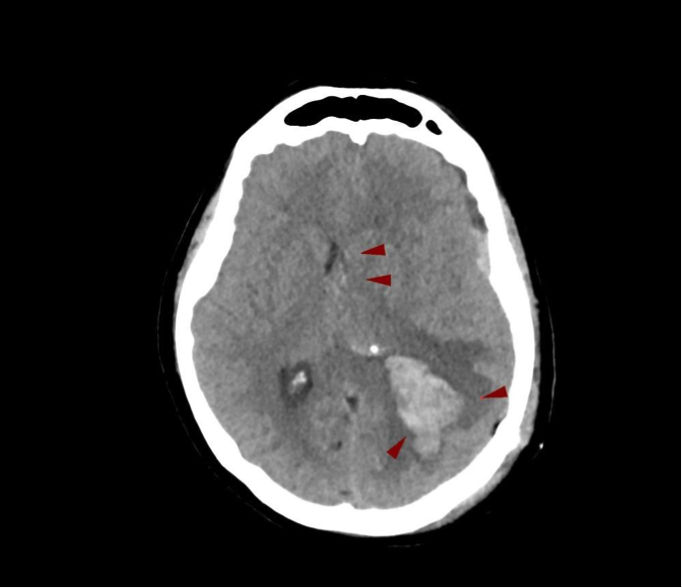

Η διάγνωση του εγκεφαλικού αιματώματος γίνεται μέσω κλινικής εκτίμησης και απεικονιστικών εξετάσεων. Η αξονική τομογραφία εγκεφάλου αποτελεί την εξέταση πρώτης γραμμής, καθώς επιτρέπει την άμεση απεικόνιση του αιματώματος στον εγκέφαλο, τον καθορισμό του μεγέθους του και την εκτίμηση της επίδρασής του στις γύρω δομές. Σε ορισμένες περιπτώσεις, η μαγνητική τομογραφία παρέχει επιπλέον πληροφορίες, ιδιαίτερα για την εγκεφαλική θλάση και τις μικρότερες αιμορραγίες.

Παράλληλα, ο νευροχειρουργός αξιολογεί τη νευρολογική κατάσταση του ασθενή, λαμβάνει λεπτομερές ιστορικό και εκτιμά πιθανούς προδιαθεσικούς παράγοντες. Η έγκαιρη και ακριβής διάγνωση είναι καθοριστική για τη λήψη της σωστής θεραπευτικής απόφασης και τη μείωση των επιπτώσεων της βλάβης